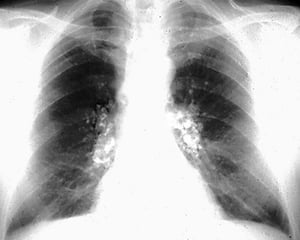

Silicosis—Simple

Image courtesy of David W. Cugell, MD.

Chronic silicosis is categorized on chest imaging as simple or complicated. In patients with simple silicosis, there is upper lobe predominance of bilateral 1- to 3-mm reticulonodular opacities. Calcified hilar and mediastinal lymph nodes are common and occasionally resemble eggshells; however, eggshell calcification is not pathognomonic for silicosis. Pleural thickening is uncommon unless a severe parenchymal disease abuts the pleura.

Complicated silicosis is characterized by large opacities on chest x-ray or conglomerate opacities with calcifications on chest CT. Imaging shows coalescing of nodules when simple silicosis progresses to complicated silicosis.